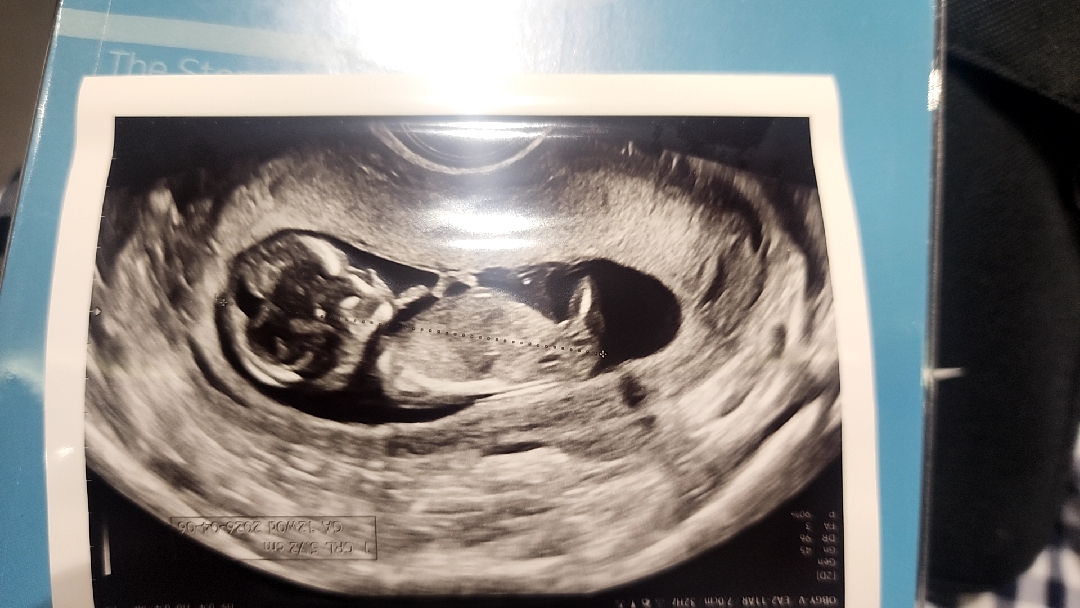

각도법으로 봐주세욤!

복댕이 각도법으로 봐주세요~^^

산부인과믄 아니지만 다른과 의사입니당 제생각에 저거는 생식기보다는 애기 한쪽 다리가 나오다 잘린 단면같아요 안에 하얀게 뼈인거같네요